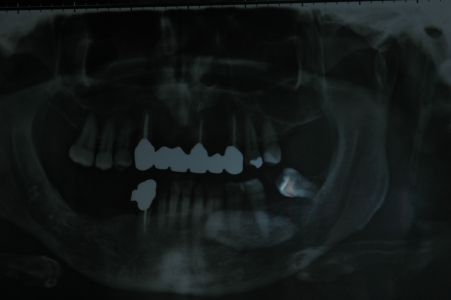

Sottoponiamo il paziente ad accertamenti diagnostici di tipo radiologico, sottoponendolo a ortopantomografia delle arcate dentarie

da cui si intravede una formazione radiopaca di forma ovalare nella regione mandibolare destra, all'ingrandimento

si rileva la continuità dei bordi. Essendo l'O.P.T. una RX bidimensionale sottoponiamo il paziente ad una RX occlusale da cui rileviamo che la formazione è dispersa nei tessuti molli del pavimento linguale.